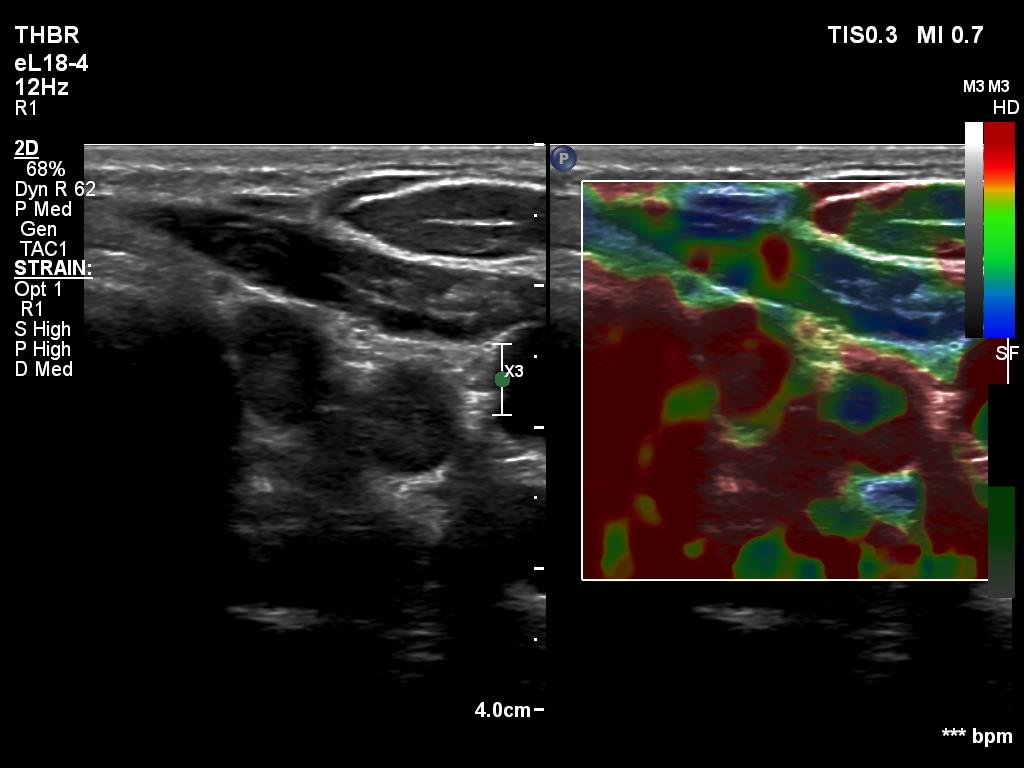

Right lobe, longitudinal scan

Left thyroid bed, transverse scan, elastography. The lesion proved to be hard on elastography.